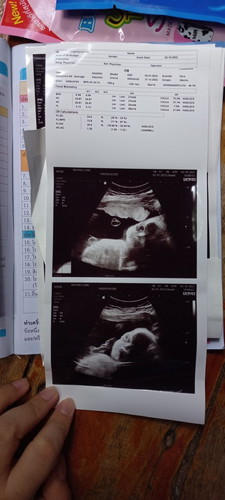

เราว่ารูปซาวด์แปลกๆ แม่ๆท่านอื่นว่าแปลกไหมคะ

ตากับหน้าดูแปลกๆ หรือว่าปกติคะ พึ่งมาดูรูปชัดๆเลยไม่ทันได้ถามคุณหมอ แม่กังวลจัง น้อง 26+6 week

ปกติค่ะท่าแรกเหมือนน้องเบะปากค่ะถ้า2น้องหาวค่ะแม่